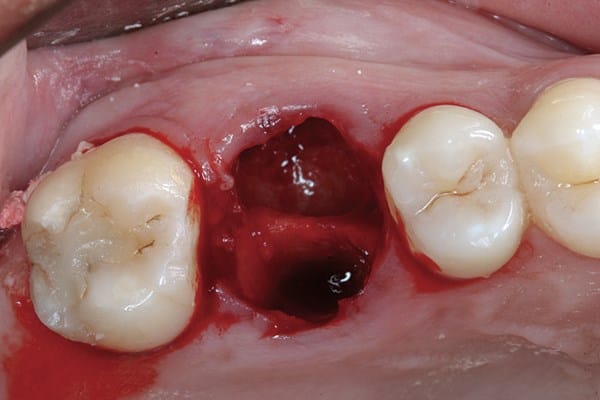

- Húmeda: El alvéolo no se encuentra vacío, se observa un tejido sangrante y oscuro. También se suele producir de 48 a 72 hs después de la extracción dental y los síntomas son mucho dolor y mal aliento y sabor. Puede ser producida por algún cuerpo extraño en la herida como restos alimenticios.

- Seca: Si uno observa el alvéolo lo encuentra vacío, sin la formación del coágulo de sangre y se puede divisar el hueso. Comúnmente los síntomas son mal aliento (halitosis) y mal sabor en la boca, como también un dolor intenso de la zona. Se suele presentar de 48 a 72 hs después de la extracción dental.